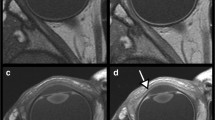

In the cadaver specimens, the optic sheath, intraorbital ON and surrounding subarachnoid spaces, and CRA coursing in the central part of the nerve were clearly identified in all sides of the three specimens, at both the level of the orbital apex and tip of the ON. In contrast, differences in appearance between the central and peripheral parts of the ON were not observed in any side. On coronal sections, the perivascular spaces of the CRA were ill-defined and not identified in any of the six ONs (Fig. 1).

a, b Coronal sections of a dissected right optic nerve at the level of the orbital apex, viewed from the front (a), and tip of the nerve, viewed from the rear (b), showing the optic sheath, intraorbital optic nerve and surrounding subarachnoid spaces, and central retinal artery coursing in the central part of the nerve. There is no difference in appearance between the central and peripheral parts of the ON. The perivascular spaces of the central retinal artery are ill-defined. CilA ciliary artery, CRA central retinal artery, EB eyeball, ON optic nerve, OS optic sheath, SAS subarachnoid space, arrow central retinal artery